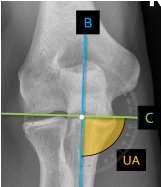

Q what is the name of this measurement? and what is the average + range?

A: Humeral angle (HA) [Elbow]

assesses the angle formed by the humeral shaft and articular lines. The average is 85°, with a range of 72-95°.

A: Ulnar angle (UA)

assesses the angle formed by the ulnar shaft and humeral articular lines. The average is 84°, with a range of 72-99°.